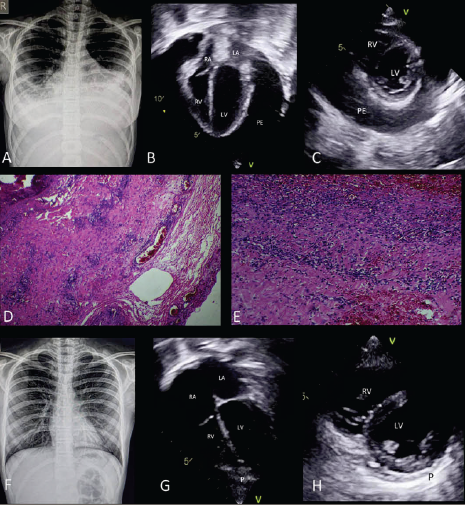

Chest Radiograph

Cardiomegaly (Fig 1)

Bilateral blunted costophrenic angles suggestive of pleural effusion (Fig 1)

Echocardiography

Structurally normal heart

Massive pericardial effusion

Diastolic collapse of the right atrium and right ventricle

Normal biventricular systolic function

Bilateral pleural effusion

Findings were consistent with the physiology of cardiac tamponade.

Pericardial biopsy confirmed an acute inflammatory infiltrate

She was asymptomatic

No residual pericardial effusion on echocardiography